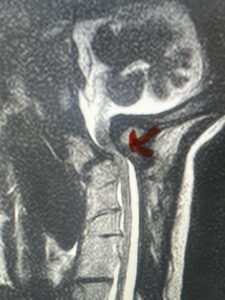

This is a 59 year-old female with a history of cerebral palsy and a prior C3-C7 posterior cervical laminectomy and instrumented fusion two years prior. She did ok until she developed progressive weakness of all four extremities and numbness. Imaging revealed she had a significant breakdown above the fusion at C2-3 with a grade 2-3 spondylolisthesis of C2 on C3 with severe spinal cord compression (Fig. 9). It was surprising the degree of anterior fusion induced by the posterior fusion from C 3-C 7 (Fig. 10). Because of her progressive neurological dysfunction in a patient who was already compromised because of her cerebral palsy, it was clearly necessary to decompress from occiput to C 3. We utilized her prior lateral mass screws although we removed bilaterally the C7 screws to reduce the fulcrum-effect on the C7-T1 junction as the C 6-7 level was solidly fused. We performed an occiput to C 6 fusion with occiput to C3 laminectomy (Fig. 11) Post operatively we had good placement and alignment (Fig. 12) The patient went to rehab with improvement of strength and numbness particularly in hands.

Fig. 9: Sagittal T2-weighted cervical MRI demonstrating severe upper cervical spinal cord compression secondary to C2 anterior subluxation on C3 with development of thickened posterior degenerative material (red arrow).